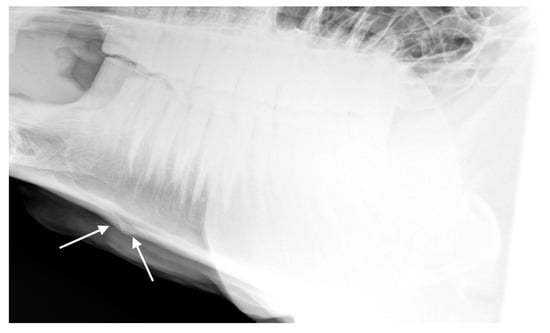

For the 32 horses where the radiologists agreed there was at least one radiographic mandible change, the radiologists agreed about the presence or absence of bone deposition in n = 22 (69%; see Figure 8), the presence or absence of loss of bone homogeneity in n = 25 (78%, see Figure 9), the presence or absence of bone thinning in n = 30 (94%), and the presence or absence of soft tissue swelling in n = 18 (56%). An example of a radiograph showing both bone thinning and bone deposition is shown in Figure 10.

Figure 10. Radiograph showing the nasal bones of a horse in which radiologists (n = 2) agreed there was both bone thinning and bone deposition.